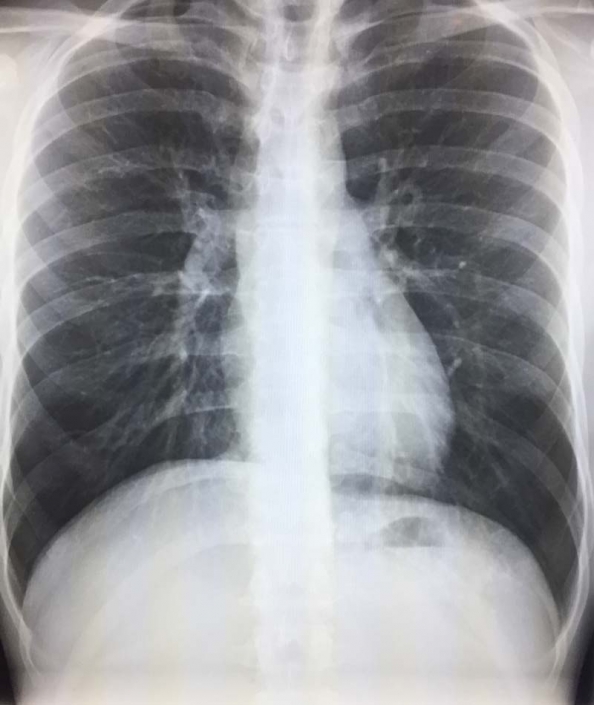

Chest X Ray Granuloma . Granulomas form in the lungs when the immune system barricades the substances it perceives as foreign but is unable to remove. Granulomas manifest with numerous imaging appearances in thoracic radiology, and their presence is a nonspecific finding. A calcified granuloma looks like a dense white spot on chest x ray replacing the normally dark lung. The most common cause of nodule calcification is granuloma formation, usually in the response to healed infection. It can be anywhere in size from a tiny dot to multiple. Depending on where it is in your body, your provider may think you have a granuloma based on a physical exam or. Lung nodules, in turn, are white specks in that black space, meaning there’s.

Granulomas manifest with numerous imaging appearances in thoracic radiology, and their presence is a nonspecific finding. Granulomas form in the lungs when the immune system barricades the substances it perceives as foreign but is unable to remove. It can be anywhere in size from a tiny dot to multiple. Depending on where it is in your body, your provider may think you have a granuloma based on a physical exam or. A calcified granuloma looks like a dense white spot on chest x ray replacing the normally dark lung. Lung nodules, in turn, are white specks in that black space, meaning there’s. The most common cause of nodule calcification is granuloma formation, usually in the response to healed infection.